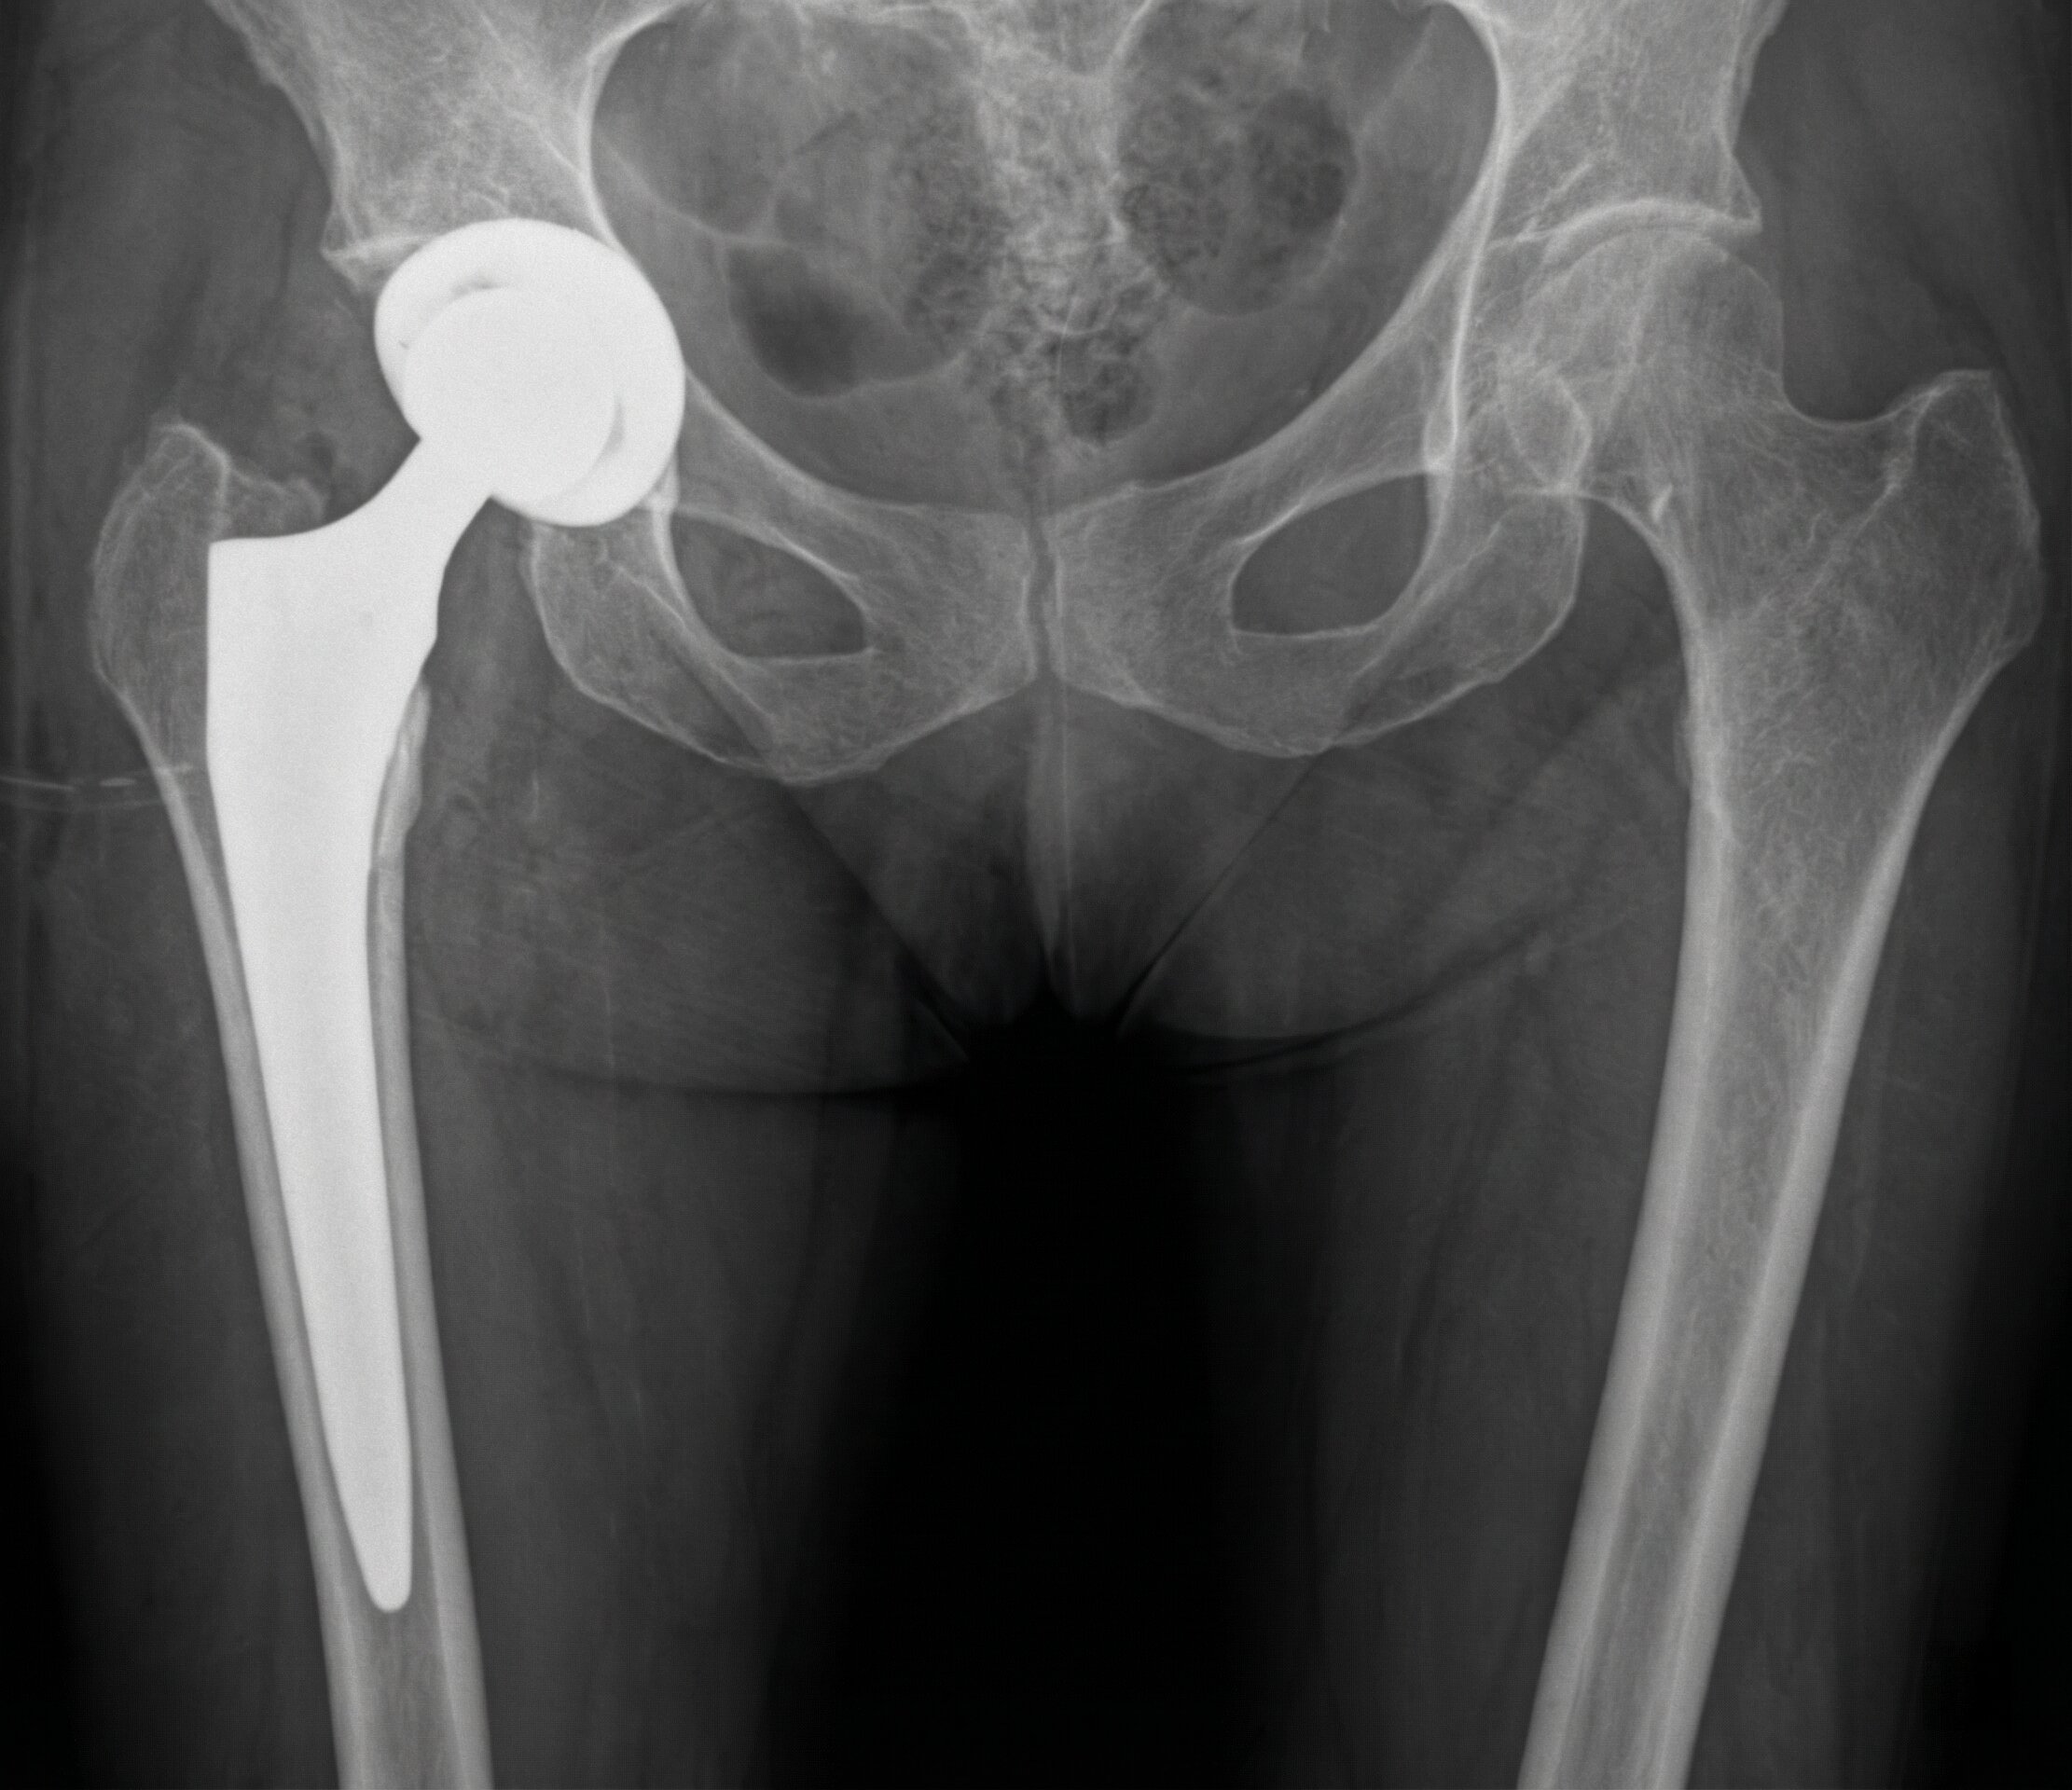

Coxartrosi: Protesi di Anca

Il trattamento iniziale è conservativo (farmaci o infiltrazioni), ma nei casi avanzati si ricorre alla protesi d’anca.

L’intervento è indicato quando il dolore compromette la qualità di vita.